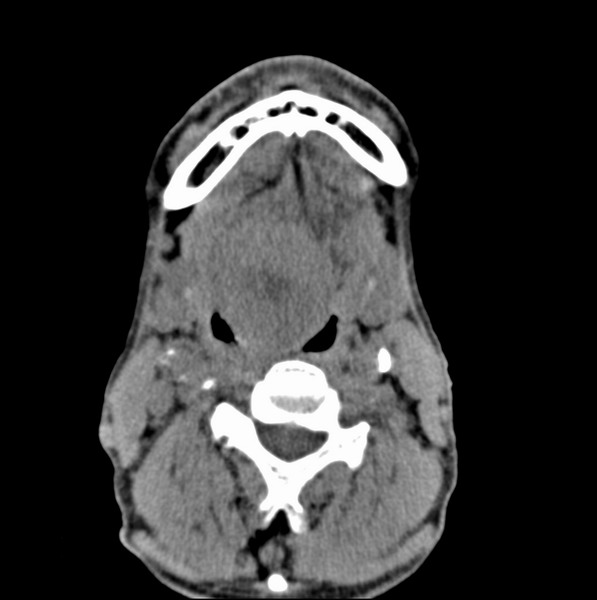

男、60、舌根肿物。

舌垂直肌和横肌影处肿块影,边缘不规则,咽腭扁桃体及舌下间隙脂肪影消失,病变侵及口咽。

考虑-----舌根癌

舌跟软组织肿块,较大有坏死,钙化。结合年龄一般是恶性肿瘤。

舌根部较大软组织肿块,其内见坏死低密度区及钙化影;考虑舌根癌可能。